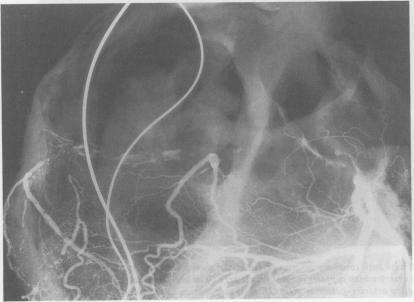

Postmortem angiography was used to examine the blood vessels supplying the sinoatrial node in 25 subjects with chronic sinoatrial disorder (group 1). The results were compared with similar studies in 54 subjects who died of heart block and in whom sinus node function was normal (group 2). Although no significant lesion obstructing the blood flow to the sinus node was seen in the majority of those in group 1, there were abnormalities in seven cases, with reduced filling of the sinus node artery in five. In group 2 the sinus node artery filled normally in all cases despite major disease of the parent vessel in three. The combination of contralateral coronary artery disease with extensive atrial anastomoses was actively sought because this arrangement might predispose to a steal phenomenon. Such conditions were fully met in three cases in group 1 and two cases in group 2, and were found to a lesser extent in a further two cases in group 1 and three in group 2. Although coronary artery disease was unlikely to be the principal cause of sinus node dysfunction in most of the cases studied it was relatively common and may have been a factor in about one third. Improved survival after myocardial infarction may increase the number of patients with chronic sinoatrial disorder of ischaemic origin.

对25例患有慢性窦房结功能障碍的受试者(第1组)进行尸检血管造影,以检查供应窦房结的血管。将结果与54例死于心脏传导阻滞且窦房结功能正常的受试者(第2组)的类似研究进行比较。尽管在第1组的大多数受试者中未发现明显阻碍窦房结血流的病变,但有7例存在异常,其中5例窦房结动脉充盈减少。在第2组中,尽管有3例患者的主干血管存在严重病变,但所有病例的窦房结动脉均正常充盈。积极寻找对侧冠状动脉疾病合并广泛心房吻合的情况,因为这种情况可能易引发窃血现象。第1组有3例、第2组有2例完全符合这些情况,第1组另有2例、第2组另有3例在较小程度上符合这些情况。尽管在所研究的大多数病例中,冠状动脉疾病不太可能是窦房结功能障碍的主要原因,但它相对常见,在约三分之一的病例中可能是一个因素。心肌梗死后生存率的提高可能会增加缺血性起源的慢性窦房结功能障碍患者的数量。